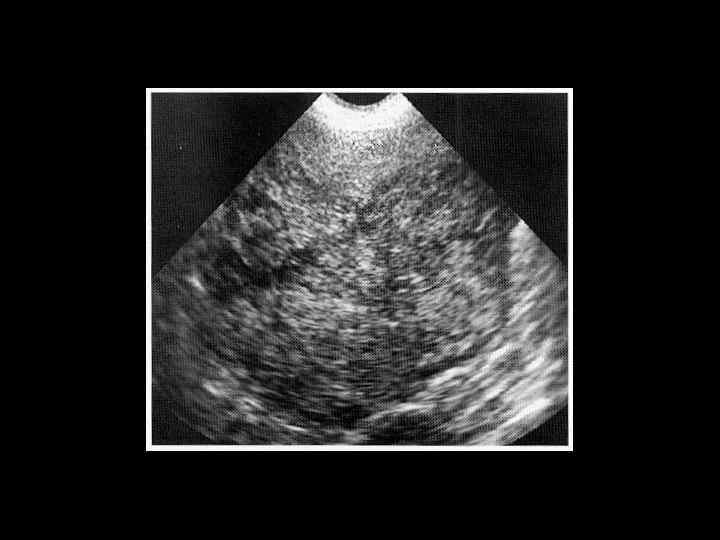

АКТУАЛЬНЫЕ ВОПРОСЫ РЕНТГЕНОЛОГИИ ЛУЧЕВАЯ ДИАГНОСТИКА ОЧАГОВЫХ ПОРАЖЕНИЙ ПЕЧЕНИ КАВЕРНОЗНАЯ ГЕМАНГИОМА Ультразвуковая семиотика: - гиперэхогенное образование округлой или овальной формы - с четкими контурами - однородной структурой

Клиническое наблюдение. Пациентка С. , 1953 г. р.